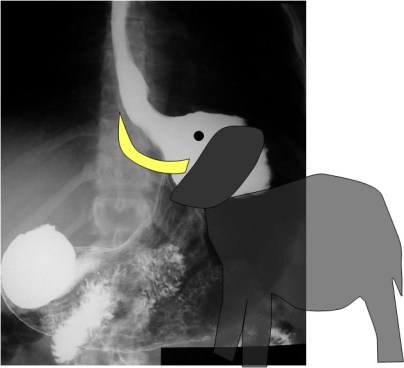

SIGNO DEL PASO AL NORTE

La misma imagen del signo anterior nos permite ilustrar este otro. En el vólvulo de sigma, la parte más alta de éste se sitúa por encima del colon transverso (marcado en amarillo en la imagen).

La imagen de TC del mismo paciente nos permite confirmar este hallazgo. A la derecha, imagen coronal. A la izquierda, imagen axial. A: sigma volvulado. B: colon transverso lleno de heces. C: ciego.

La denominación en inglés de este signo es «the northern exposure sign». La traducción literal (signo de la exposición del norte) resulta incomprensible por carecer de sentido. En el artículo donde se describe (Javors BR, Baker SR, Miller JA. The northern exposure sign: a newly described finding in sigmoid volvulus. AJR Am J Roentgenol. 1999;173 (3): 571-4) los autores refieren que, si el colon transverso puede considerarse el ecuador del abdomen, el sigma normalmente ocupa el hemisferio sur, caudal al colon transverso -inframesocólico-. El signo se observa cuando el ápex del colon sigmoide ha migrado cefálicamente, por encima del colon transverso, al espacio supramesocólico. De ahí que hayamos preferido traducirlo como Signo del paso al norte.